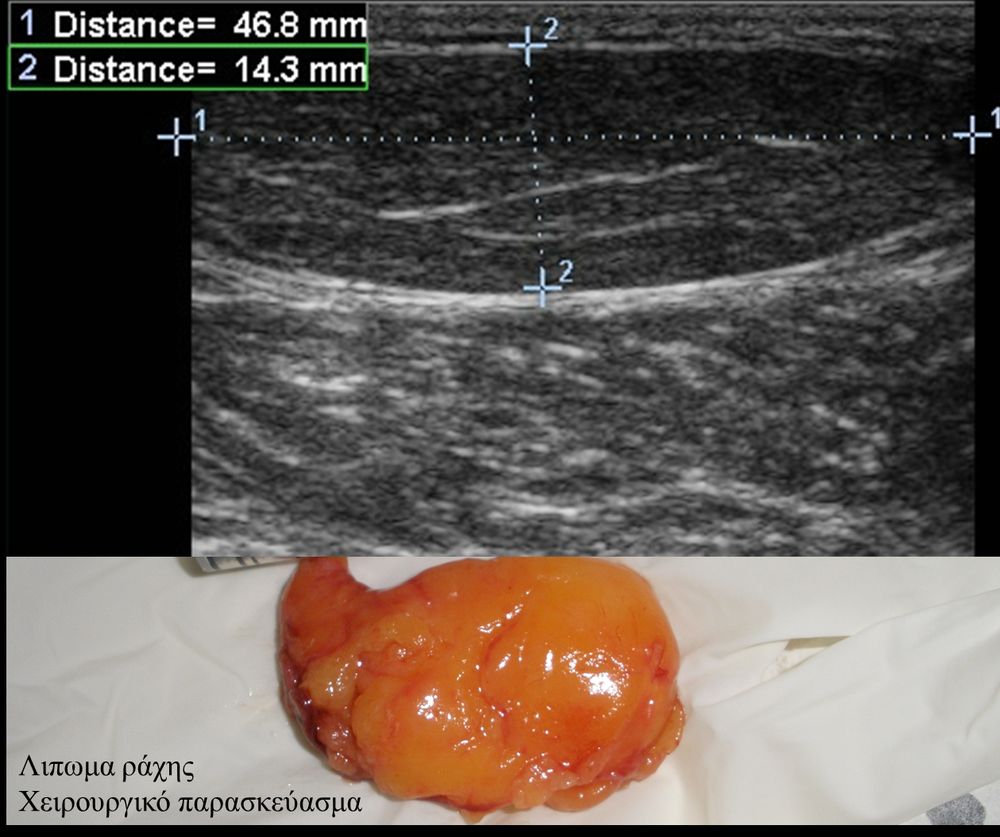

Πρόκειται για υπερηχογράφημα υψηλής ευκρίνειας που επιτρέπει την λεπτομερέστατη απεικόνιση (σε επίπεδο χιλιοστού) ακόμη και πολύ μικρών/επιφανειακών ανατομικών δομών και απαιτεί ειδικό υπερηχογραφικό εξοπλισμό καθώς και εξειδίκευση του ακτινολόγου. Η εξέταση γίνεται με δυναμικό τρόπο, δηλ εκτελούνται δοκιμασίες κίνησης του μέλους που πάσχει, ώστε να αποκαλυφθεί η παθολογίαακόμη και όταν δεν είναι εμφανής σε θέση ηρεμίας. Επιπλέον, η εξέταση είναι ανώδυνη και ασφαλής και δεν περιλαμβάνει ακτινοβολία (CT), μαγνητικό πεδίο (MRI) ή παραμονή σε κλειστό χώρο και είναι πολύ ανεκτή τόσο σε ενήλικες όσο και σε παιδιά.